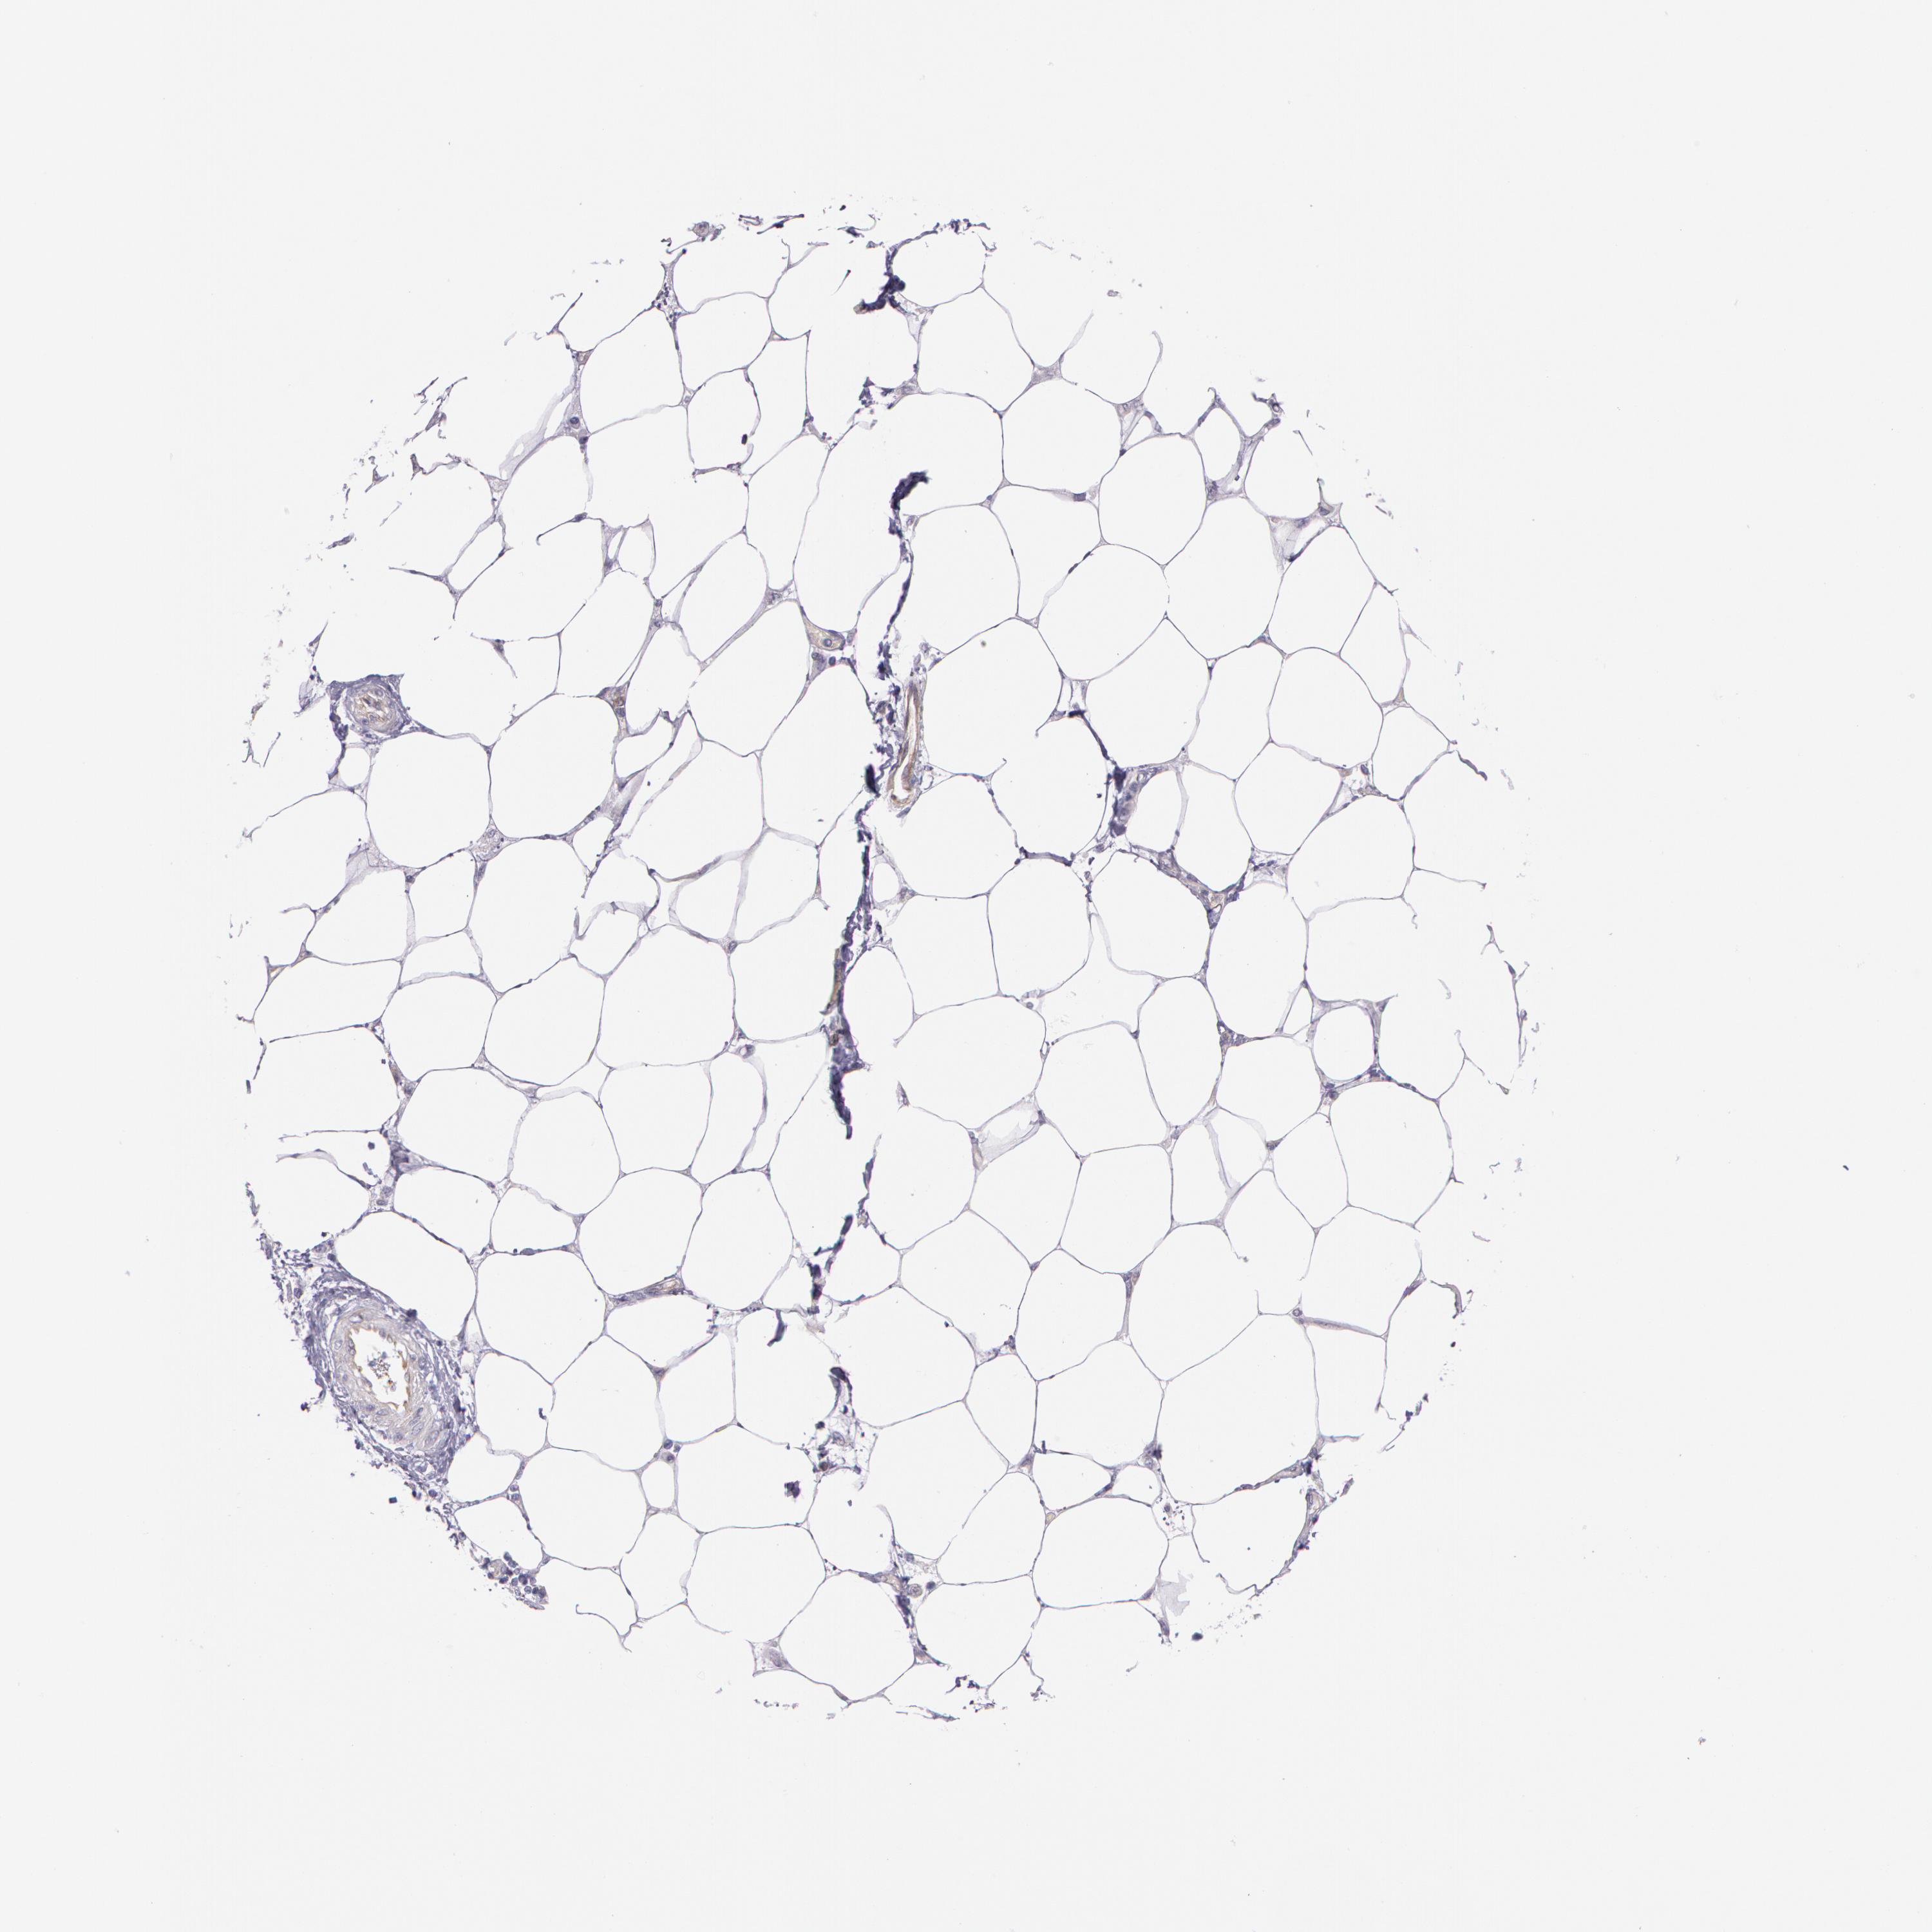

PANCREATIC CANCER - Protein expressioni

A mouse-over function shows sample information and annotation data. Click on an image to view it in a full screen mode. Samples can be filtered based on level of antibody staining by selecting one or several of the following categories: high, medium, low and not detected. The assay and annotation is described here.

Note that samples used for immunohistochemistry by the Human Protein Atlas do not correspond to samples in the TCGA dataset.

Antibody stainingi

Antibody staining in the annotated cell types in the current human tissue is reported as not detected, low, medium, or high, based on conventional immunohistochemistry profiling in selected tissues. This score is based on the combination of the staining intensity and fraction of stained cells.

Each image is clickable and will lead to virtual microscopy that enables deeper exploration of all samples and also displays staining intensity scores, fraction scores and subcellular localization as well as patient and tissue information for each sample.

Antibody HPA001462

Antibody CAB000157

Adenocarcinoma, NOS